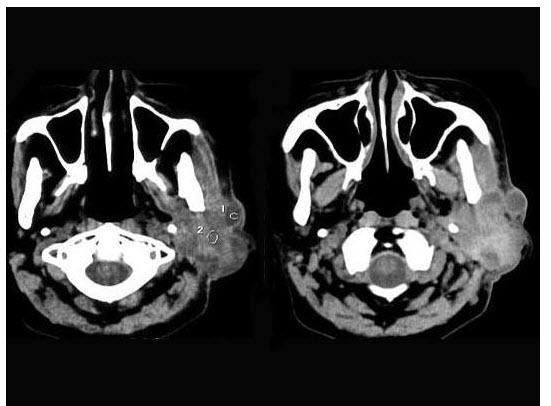

2、单项选择题 鼻咽癌病人CT显示咽旁间隙向哪个方向移位()

A.向内

B.向外

C.向前

D.向后

E.向下